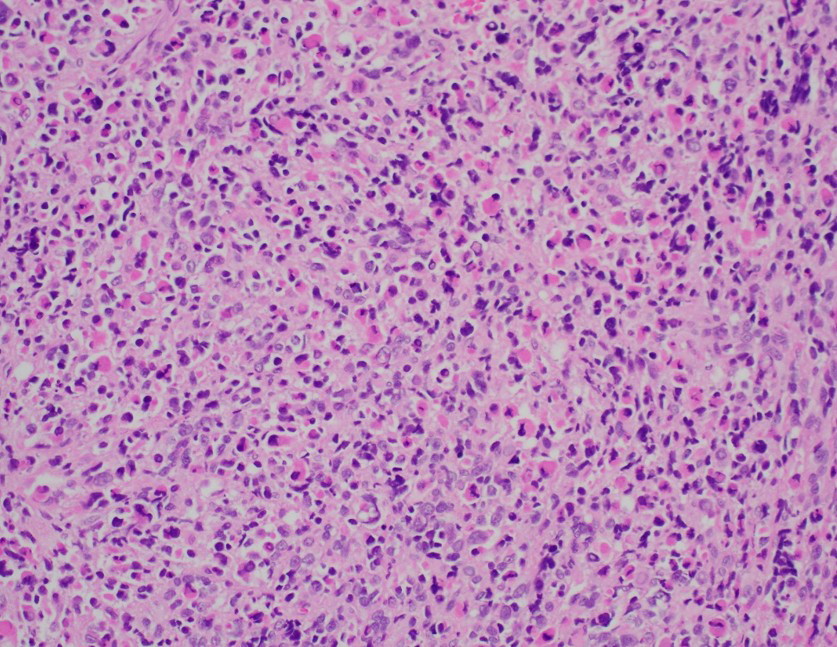

Histologic sections demonstrated a primitive small round blue cell neoplasm arranged in sheets (image 1). The tumor cells were round to polygonal with high nuclear-to-cytoplasmic ratios, vesicular chromatin, prominent nucleoli, and brisk mitotic activity (image 2). Scattered multinucleated tumor cells were identified in addition to cells with eccentrically placed nuclei and abundant eosinophilic cytoplasm (images 3 and 4). Immunohistochemistry showed strong desmin (image 5) and myogenin positivity (image 6) and focal MyoD1 supportive of skeletal muscle differentiation. Stains for cytokeratin, S100, CD45, CD99, and CD34 were negative, excluding epithelial, neural, lymphoid, and vascular neoplasms.